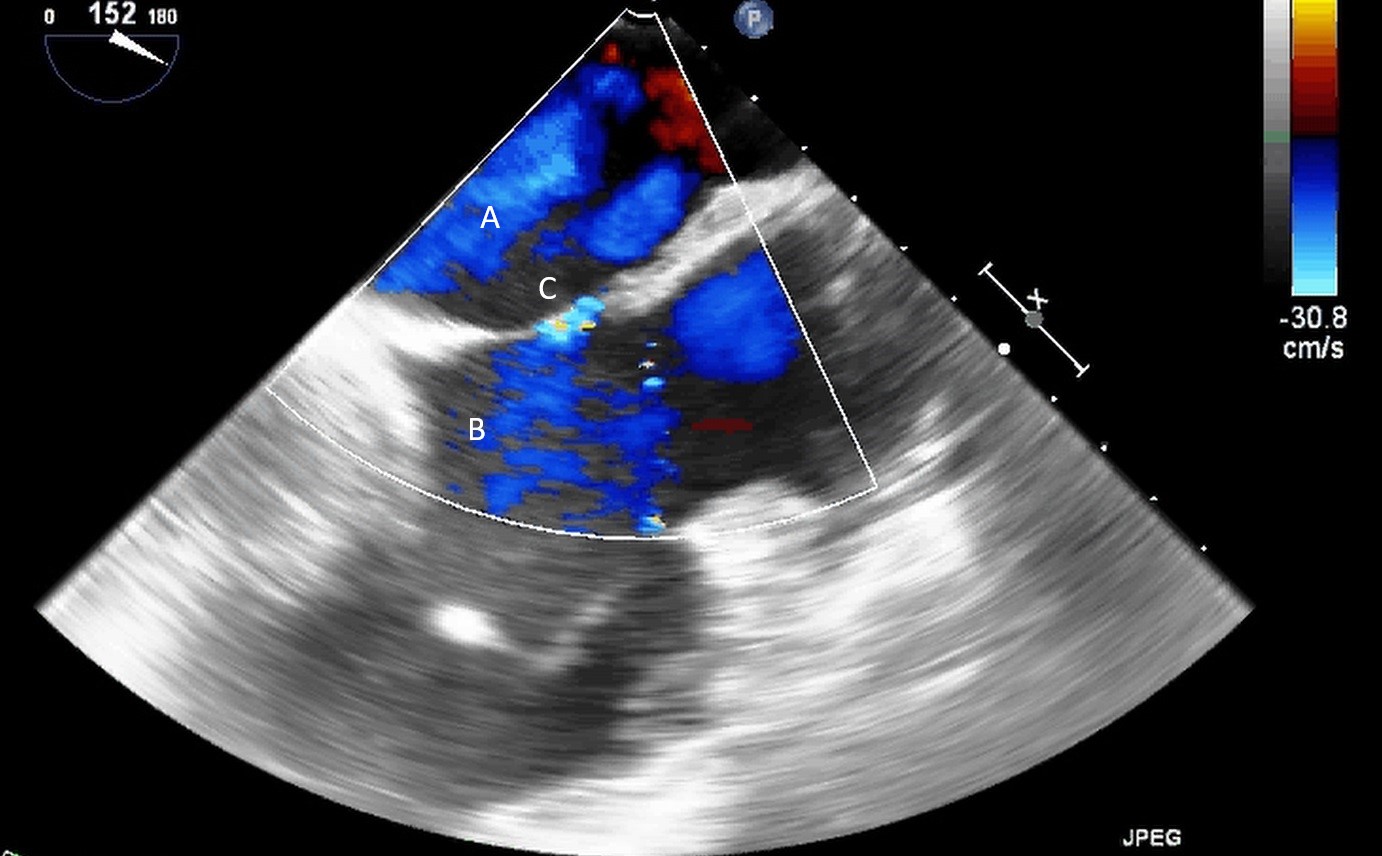

Both TTE and TEE can help with ideal positioning of the Impella (Figs. 5,6). The distance from the aortic valve to the Impella inlet should be measured. This should ideally be 3.5–4 cm for all Impella devices except for the Impella 5.5 for which it is 5 cm [15] (Fig. 7). The outlet should be 1.5–2 cm above the sinuses of Valsalva. The catheter should be angled towards the LV apex and away from the septum and mitral valve. The positioning of both the inlet in the LV cavity and the outlet above the aortic valve should be confirmed. Color flow doppler imaging can help confirm this positioning as a mosaic pattern will be visualized near the inlet and outlet ports on spectral doppler (Fig. 8). Real-time 3D echocardiography can also be used to help in visualizing Impella positioning relative to other anatomical structures (Fig. 9). After placement of the Impella, the aortic and mitral valves should be interrogated for any new or worsening regurgitation or dysfunction [16]. TEE can also help identify additional complications of Impella placement including pericardial effusion or LV free wall rupture [17].

Fig. 8.A parasternal long axis view on a transthoracic echocardiogram zoomed up on the aortic valve. Color flow imaging demonstrates a mosaic pattern at the Impella outlet, confirming its position as being above the aortic valve. (A) Impella outlet. (B) Mosaic pattern at Impella outlet on color flow doppler.

Fig. 9.Real time 3D TEE imaging visualizing the Impella in relation to the aortic valve and LVOT. (A) Impella. (B) Ascending aortic root.